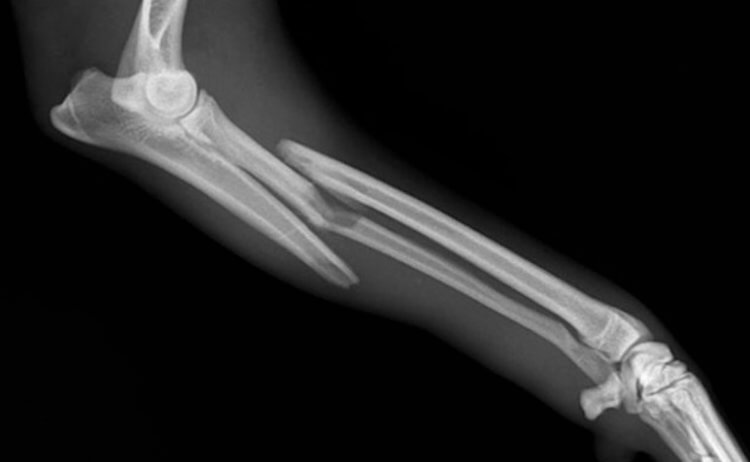

Помимо волос и ногтей, в человеческом теле восстанавливаются кости. Ведь иначе как объяснить то, что при переломах у людей срастаются кости? Также к регенерации способна печень. При утрате части печени до 85%, оставшиеся фрагменты начинают увеличиваться в размерах. Но важно понимать, что это происходит не из-за роста количества клеток, а благодаря увеличению их размера. Удивительно, но таким образом печень может восстановить свою первоначальную массу.

Скорость срастания костей зависит от тяжести перелома. Обычно требуется не менее месяца